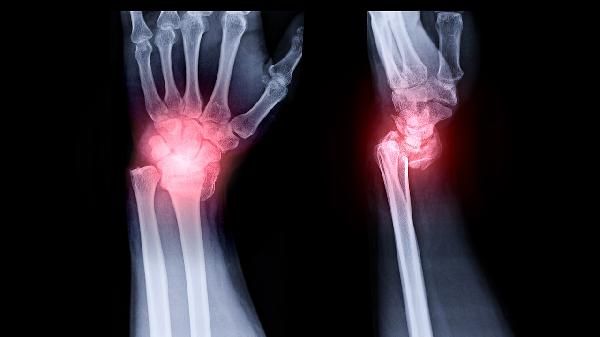

年增长超过2毫米建议手术干预。快速生长的骨瘤需排除骨化纤维瘤等病变,通过连续影像对比确认生长速度,若压迫邻近眼眶或颅底结构,需耳鼻喉科联合口腔颌面外科会诊。

骨瘤导致窦腔引流障碍需手术切除。当骨瘤占据上颌窦腔50%以上容积,或导致黏液囊肿形成时,可采用鼻内镜下微创手术,术中配合导航系统精准切除。